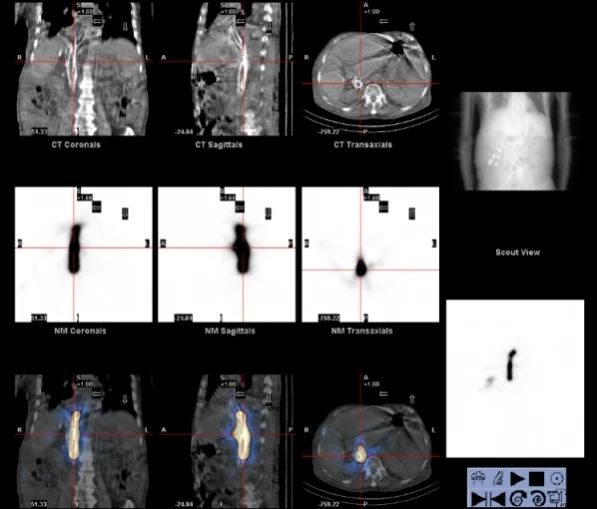

术后ECT扫描验证,碘125粒子辐射范围完全覆盖下腔静脉癌栓